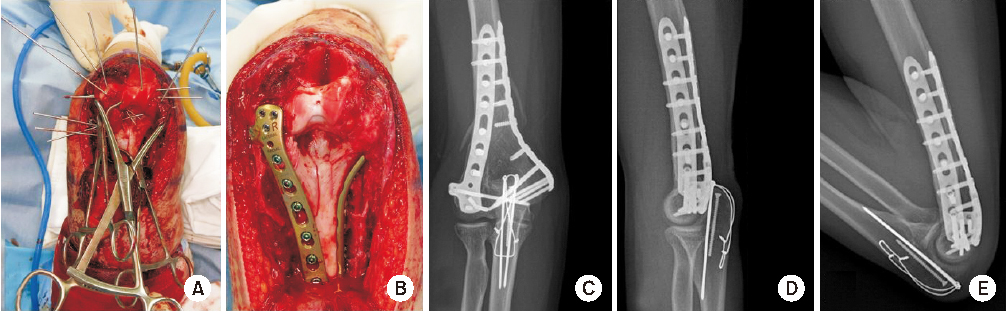

Fig. 6

Type 3 fracture. (A) Multiple comminuted articular bony fragment was reduced and fixed with K-wire. (B) Plate and screw was substituted by K-wire. (C–E) Postoperative X-ray showed stable reduction and normal range of motion.